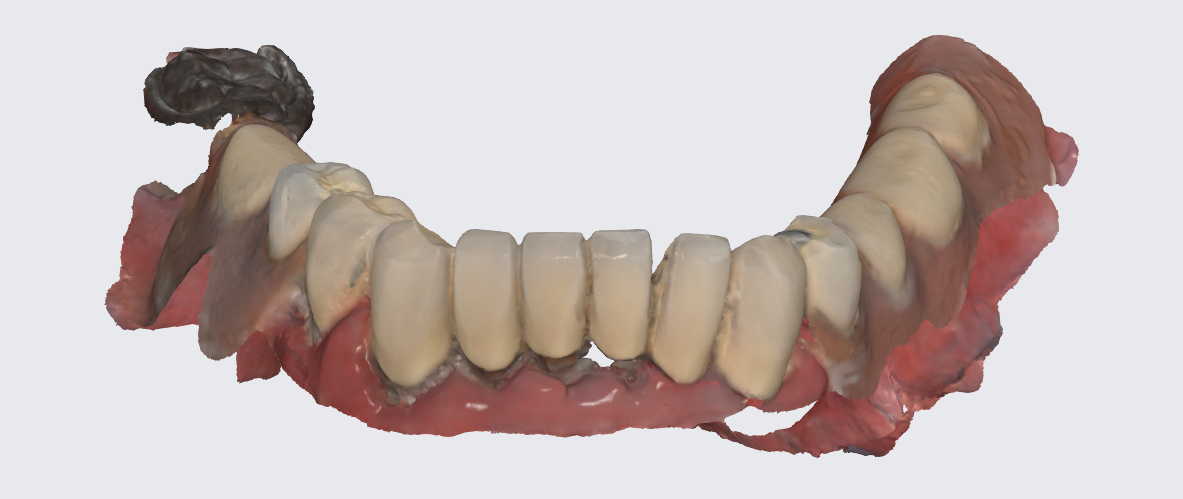

After the same procedure was performed on the mandible a new set of dentures with corrected occlusal plane was produced and we waited for approximately 6 months that passed with uneventful healing.

To prepare for the maxillary all on X procedure patient had the upper denture relined with impression material and also multiple dots of radio opaque filling material where temporarily placed on the said denture. Then the 2 dentures where scanned. Also scans of the healed tissues and of the face where recorded.

Using the Aoralscan Elite intraoral scanner (Shining 3D), detailed scans of edentulous ridges and interim prostheses were recorded efficiently and accurately. Edentulous arch scanning proved precise and rapid, significantly simplifying the workflow.